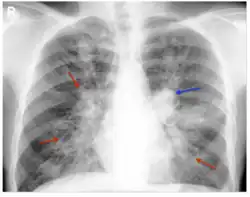

Consolidation and mucoid impaction are the most commonly described radiological features described in ABPA literature, though much of the evidence for consolidation comes from before the development of computed tomography (CT) scans. Tramline shadowing, finger-in-glove opacities, and 'toothpaste shadows' are also prevalent findings.[28]

When using high-resolution CT scans, there can be a better assessment of the distribution and pattern of bronchiectasis within the lungs, and hence this is the tool of choice in the radiological diagnosis of ABPA. Central (confined to medial two-thirds of the medial half of the lung) bronchiectasis that peripherally tapers bronchi is considered a requirement for ABPA pathophysiology, though in up to 43% of cases, there is a considerable extension to the periphery of the lung.[1]

Mucoid impaction of the upper and lower airways is a common finding.[1] Plugs are hypodense but appear on CT with high attenuation (over 70 Hounsfield units[29]) in up to 20% of patients. Where present it is a strong diagnostic factor of ABPA and distinguishes symptoms from other causes of bronchiectasis.[11]

CT scans may more rarely reveal mosaic-appearance attenuation, centrilobular lung nodules, tree-in-bud opacities, and pleuropulmonary fibrosis (a finding consistent with CPA, a disease with ABPA as a known precursor).[1] Rarely other manifestations can be seen on CT scans, including military nodular opacities, perihilar opacities (that mimic hilar lymphadenopathy), pleural effusions and pulmonary masses. Cavitation and aspergilloma are rarer findings, not exceeding 20% of patients, and likely represent a shift from ABPA to CPA if accompanied by pleural thickening or fibrocavitary disease.[11]